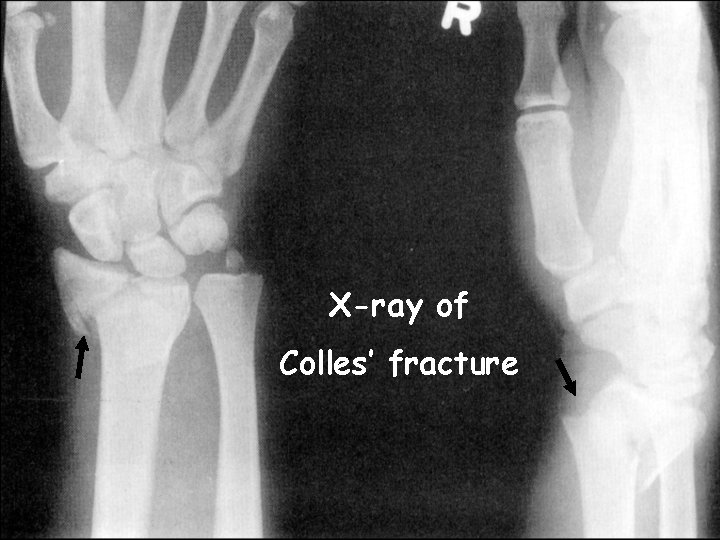

Colles’ Fracture (broken wrist)

X-ray of Colles’ fracture